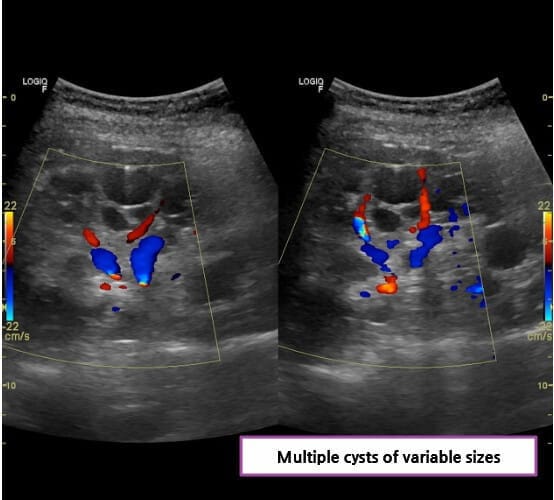

다낭성 신질환 (Polycystic Kidney Disease)

[특징]

양측 신장에 다수의 낭종으로 신장이 비대해지고, 조기 고혈압과 통증·혈뇨·감염이 잦습니다.

간낭종, 두개강내 동맥류, 판막질환 등 신외 합병증이 동반될 수 있습니다.

[임상양상]

옆구리 통증(낭종 팽창/출혈), 육안적 혈뇨, 재발성 상부 UTI·낭종 감염, 신장결석(요산/칼슘) 등이 흔합니다.

가족력이 단서가 되며, 신장 초음파에서 다발성 낭종이 확인됩니다.

다낭성 신질환 (Polycystic Kidney Disease, PKD)

양측 신장에 다수의 낭종

조기 고혈압 및 신기능 저하

간낭종, 뇌동맥류 등 신외 합병증 동반

[정의]

다낭성 신질환은 유전적 이상으로 인해 신실질에 다수의 낭종이 발생하여 점차 커지고, 결국 신장이 비대해지면서 만성 신부전으로 진행하는 질환입니다.

[진단]

– 신장 초음파에서 다수의 낭종을 확인하여 진단합니다.

– CT/MRI에서 낭종의 분포와 크기를 정밀하게 평가하며, 총신장용적(TKV)을 측정하여 예후를 예측합니다.